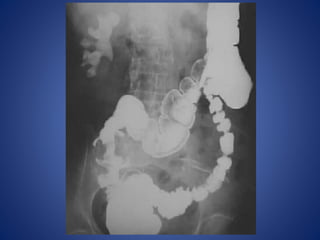

DIAGNOSIS ?

Hernia

Paralytic Ileus

DIAGNOSIS

Small bowel obstruction

Large bowel obstruction